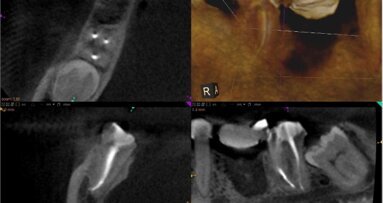

Celem niniejszego artykułu jest przedstawienie przydatności badania tomograficznego wiązki stożkowej w ocenie anatomii oraz jakości wypełnienia ...

Celem niniejszego artykułu jest przedstawienie przydatności badania tomograficznego wiązki stożkowej w ocenie anatomii oraz jakości wypełnienia ...